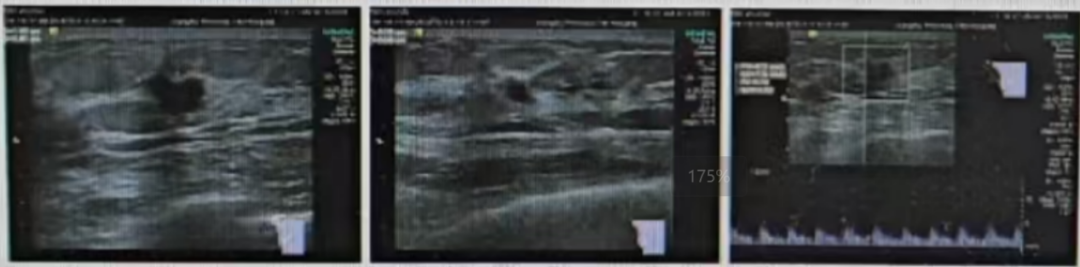

·乳腺钼靶

1、双乳腺体密度混合型ACR c型;

2、双乳小叶增生伴瘤化;右乳外上象限多发结节,考虑BIRADS 4B类,建议进一步MR检查。

图2乳腺DR结果